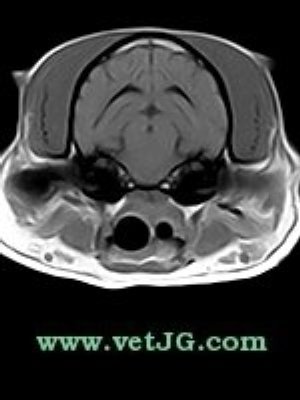

RESONANCIA MAGNÉTICA

AXIAL